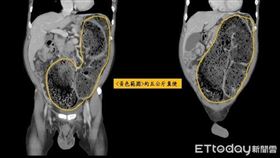

苗栗男便秘捅破直腸!宿便倒灌腹腔險喪命

苗栗一名65歲黃姓男子,長期飽受便秘所苦,因飲食控制...